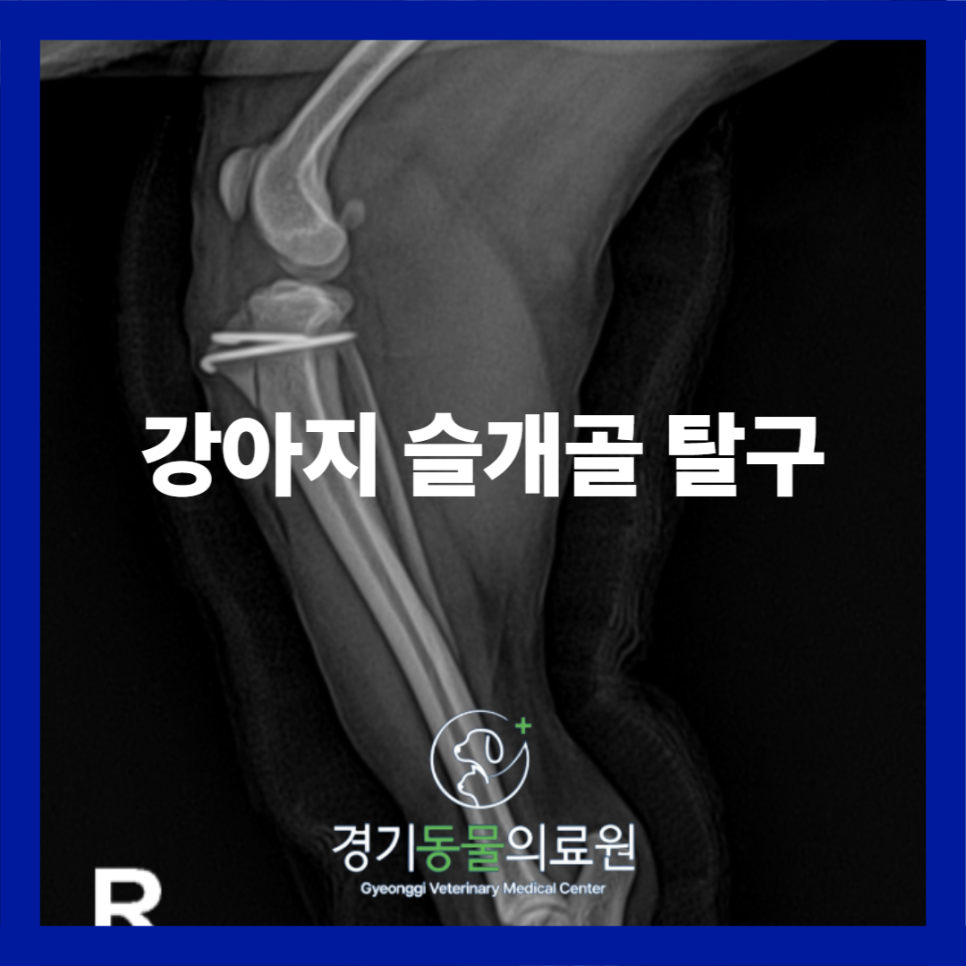

▶ 수술 전 방사선 검사

방사선 검사 상에서도 양측의 내측 슬개골탈구가 확인되었습니다.